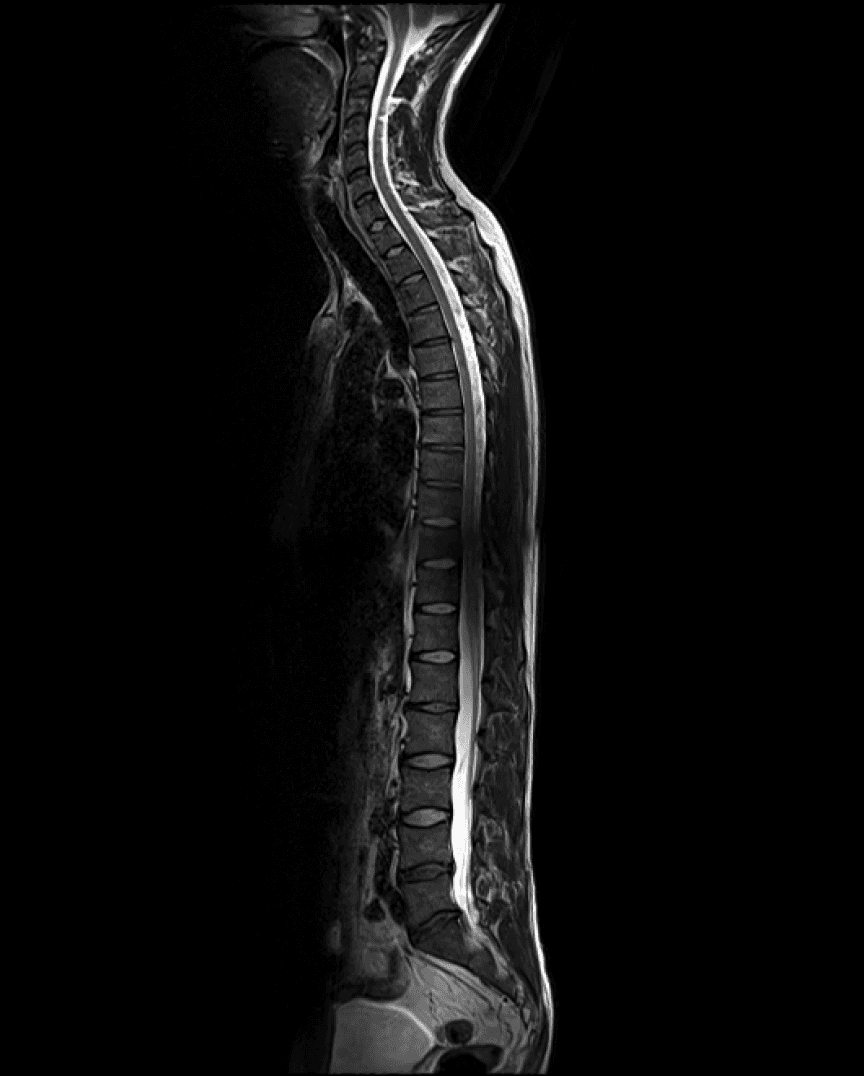

Ihr aktueller Check-up bietet einen detaillierten Überblick über Ihre Gesundheit und zeigt einige sehr positive Entwicklungen sowie einige Bereiche, die Aufmerksamkeit verdienen. Die auffälligsten Befunde betreffen altersgerechte Abnutzungserscheinungen in Ihrer Wirbelsäule.

KI-basierte Annotation Ihres Körpers

Verstehen Sie hochkomplexe Scan-Ergebnisse.

Mehr als eine Momentaufnahme

Verfolgen Sie Veränderungen über Jahre hinweg.